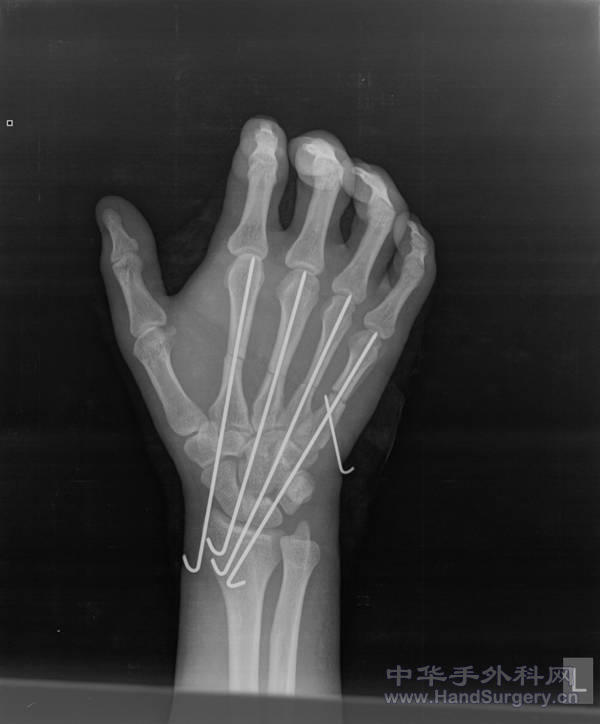

左手多发掌骨骨折X片

患者因机器挤压伤入院,左手多发掌骨骨折,入院后给予切开复位克氏针内固定术,本人认为克氏针内固定不通过掌指关节对手的功能影响较小,且克氏针固定手术简单,愈合快。